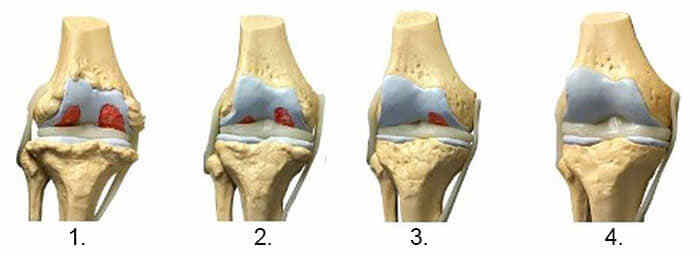

На зображенні нижче показана типова картина відновлення колінного суглоба.